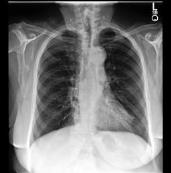

Large numbers of labeled medical images are essential for the accurate detection of anomalies, but manual annotation is labor-intensive and time-consuming. Self-supervised learning (SSL) is a training method to learn data-specific features without manual annotation. Several SSL-based models have been employed in medical image anomaly detection. These SSL methods effectively learn representations in several field-specific images, such as natural and industrial product images. However, owing to the requirement of medical expertise, typical SSL-based models are inefficient in medical image anomaly detection. We present an SSL-based model that enables anatomical structure-based unsupervised anomaly detection (UAD). The model employs the anatomy-aware pasting (AnatPaste) augmentation tool. AnatPaste employs a threshold-based lung segmentation pretext task to create anomalies in normal chest radiographs, which are used for model pretraining. These anomalies are similar to real anomalies and help the model recognize them. We evaluate our model on three opensource chest radiograph datasets. Our model exhibit area under curves (AUC) of 92.1%, 78.7%, and 81.9%, which are the highest among existing UAD models. This is the first SSL model to employ anatomical information as a pretext task. AnatPaste can be applied in various deep learning models and downstream tasks. It can be employed for other modalities by fixing appropriate segmentation. Our code is publicly available at: https://github.com/jun-sato/AnatPaste.